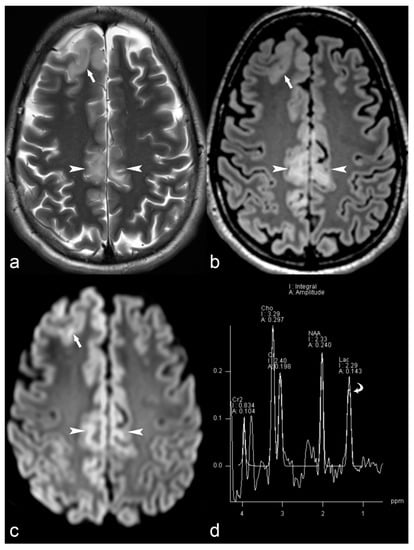

Figure 5.

10-year-old girl with cortical dysplasia. There is thickening of the cortex on the left mesial fronto-parietal region (arrows in (a) to (f)) associated to funnel-shaped hyperintensity of the surrounding white matter (arrows in (b,e)). Note blurring between the white and gray matter interface (f).